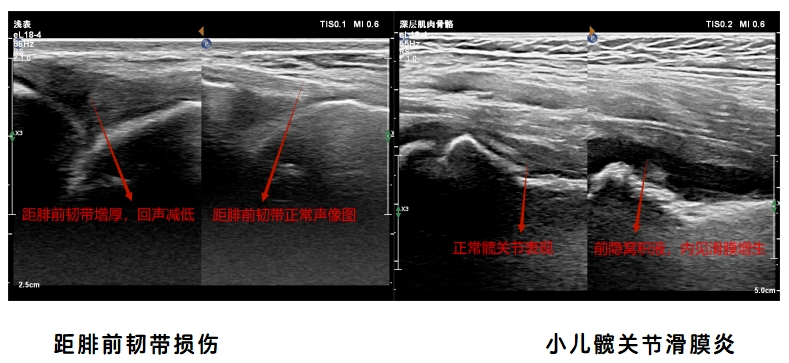

6.踝关节超声检查:踝管综合征、跟腱断裂、跟腱止点炎、崴脚后所致韧带损伤(距腓前韧带、跟腓韧带、胫腓前韧带、胫腓后韧带、距腓后韧带)、腓骨长短肌损伤、跖腱膜纤维瘤样增生、足底筋膜炎、痛风性关节炎,类风湿性关节炎等。

4.髋关节超声检查:梨状肌综合征(坐骨神经卡压)、阔筋膜张肌肌腱病、小儿髋关节滑膜炎、坐骨结节滑囊炎、小儿发育性髋关节发育不良 (DDH)等。

病例图像